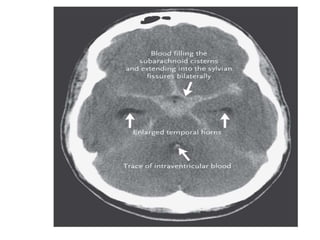

CT BRAIN

• In the first 3 days after the onset of symptoms, sensitivity is

close to 100% subsequently declines to 50% by 5 to 7 days

• If CT is negative but clinical suspicion is high, additional

tests are indicated.

• CT may also show a space-occupying hematoma or acute

hydrocephalus — consequences of aneurysm rupture, this

needs immediate surgical attention.